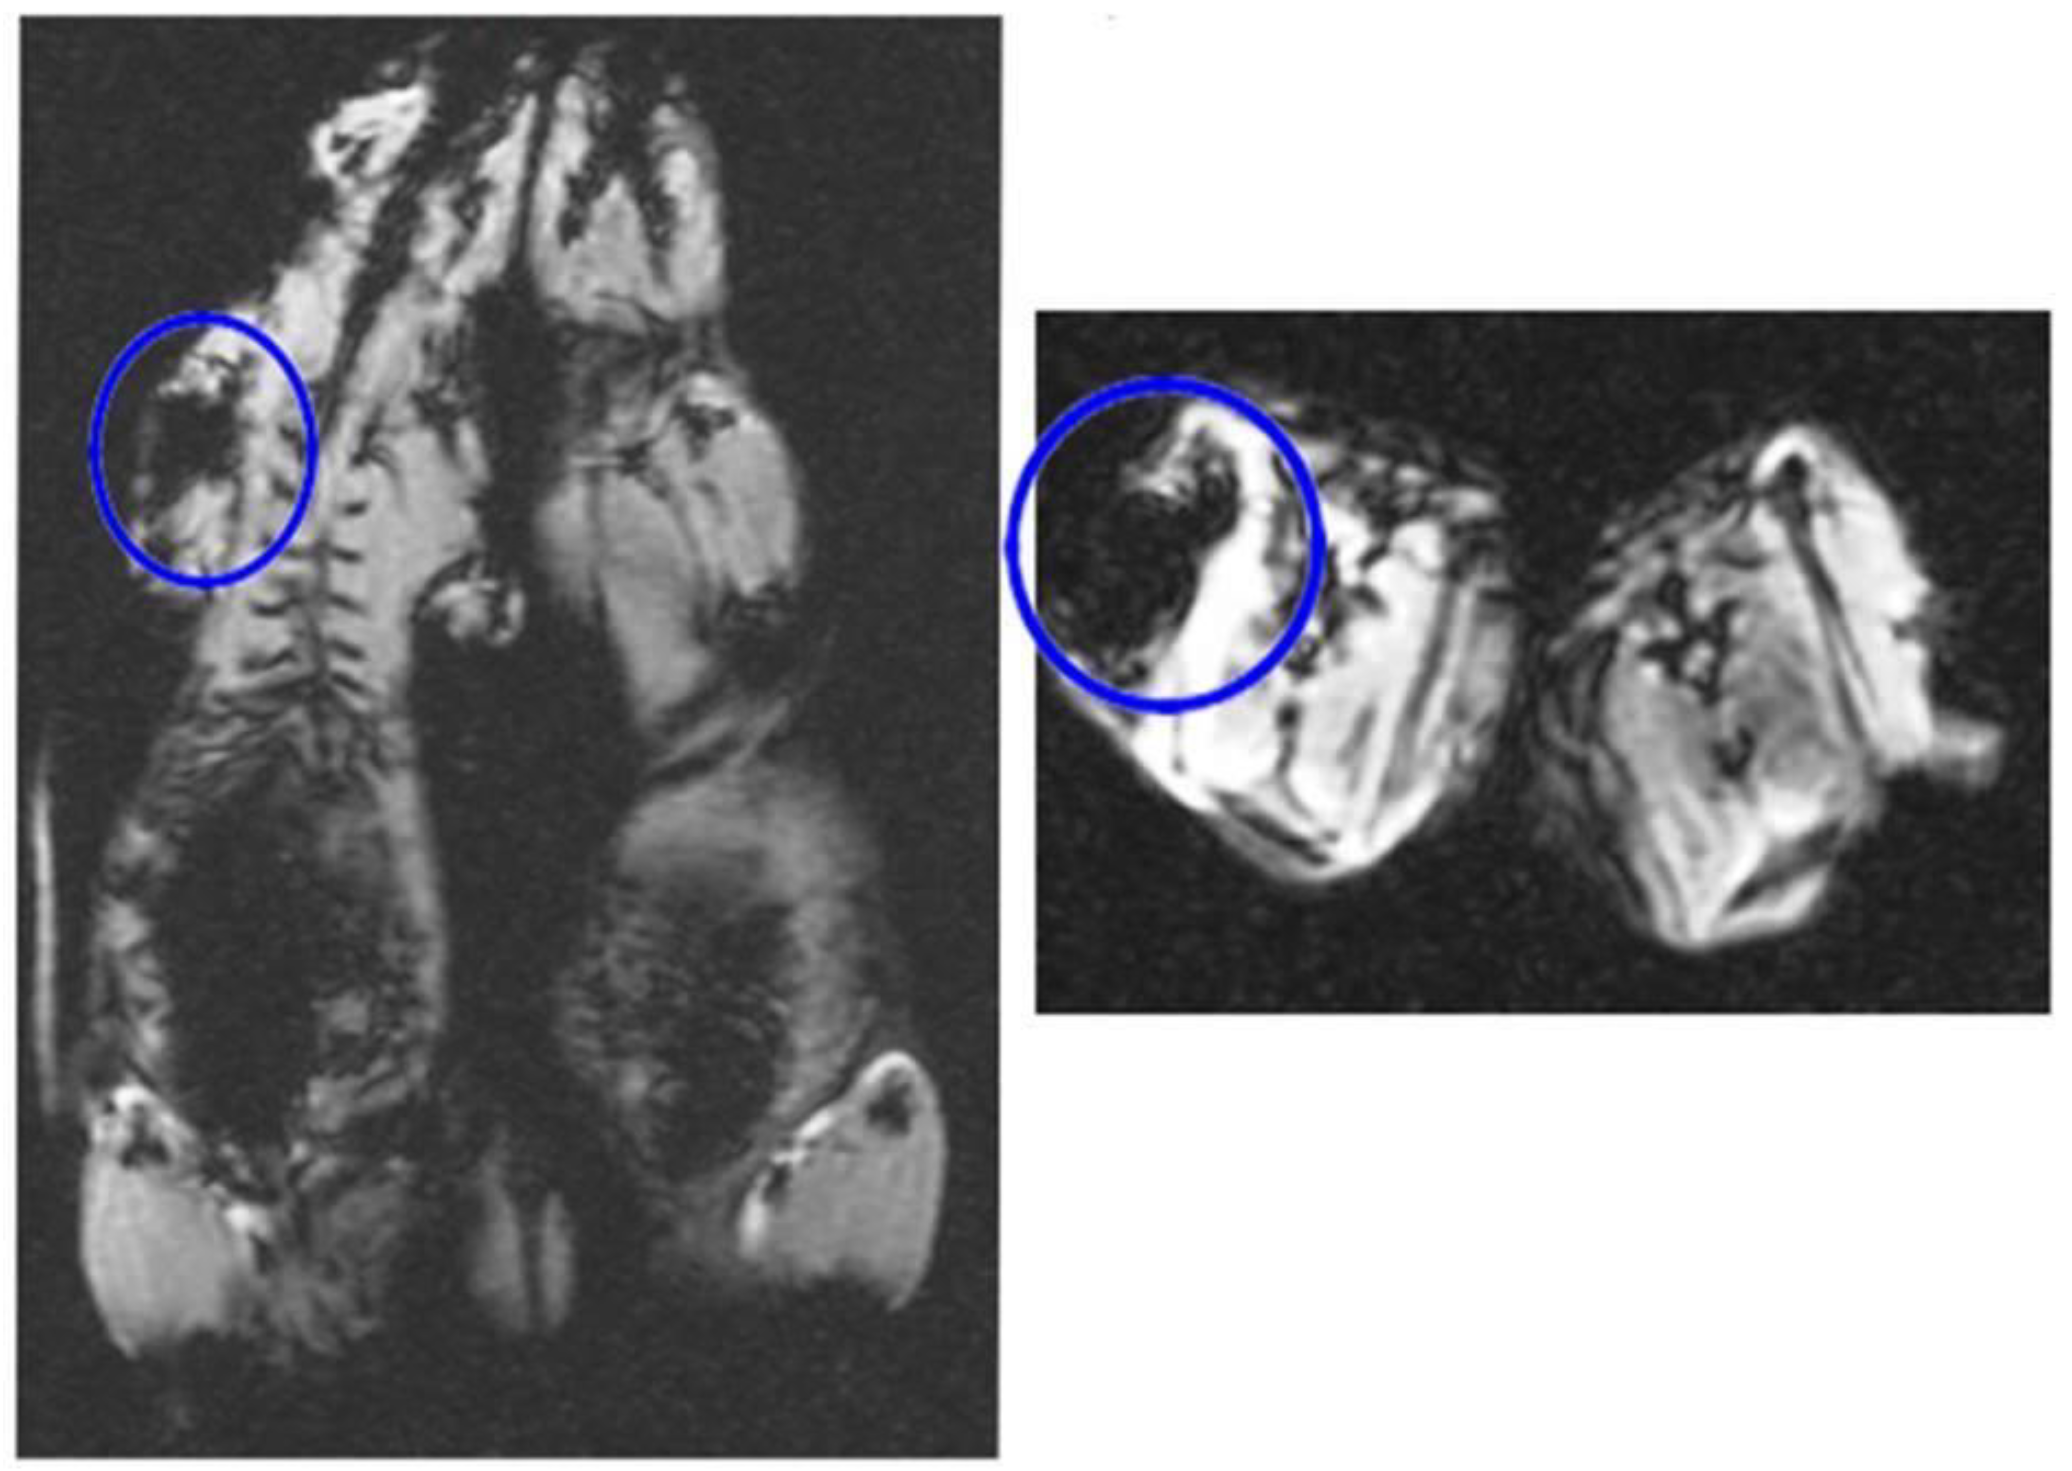

Figure 5 in in vivo MRI tracking after intraperitoneal injection of DPSCs labeled with 180 µg/mL of iron oxide transfected with 1 µL/mL lipofectamine confirmed presence of iron oxide in the labeled cells transfected with lipofectamine in the peritoneal cavity. The T2* weighted images of in vivo samples in the right picture displays the hypo-intense signal of the iron oxide contrast compared to non-labeled cells in the left picture lacking this MRI appearance.

Figure 5.

The T2* weighted images of in vivo samples showing the hypo-intense signal of 180 µg/mL of iron oxide labeled DPSCs transfected with 1 µL/mL lipofectamine that confirms presence of iron oxide in the labeled cells in comparison to in vivo samples of non-labeled cells showing lack of this MRI appearance (Left and Right).